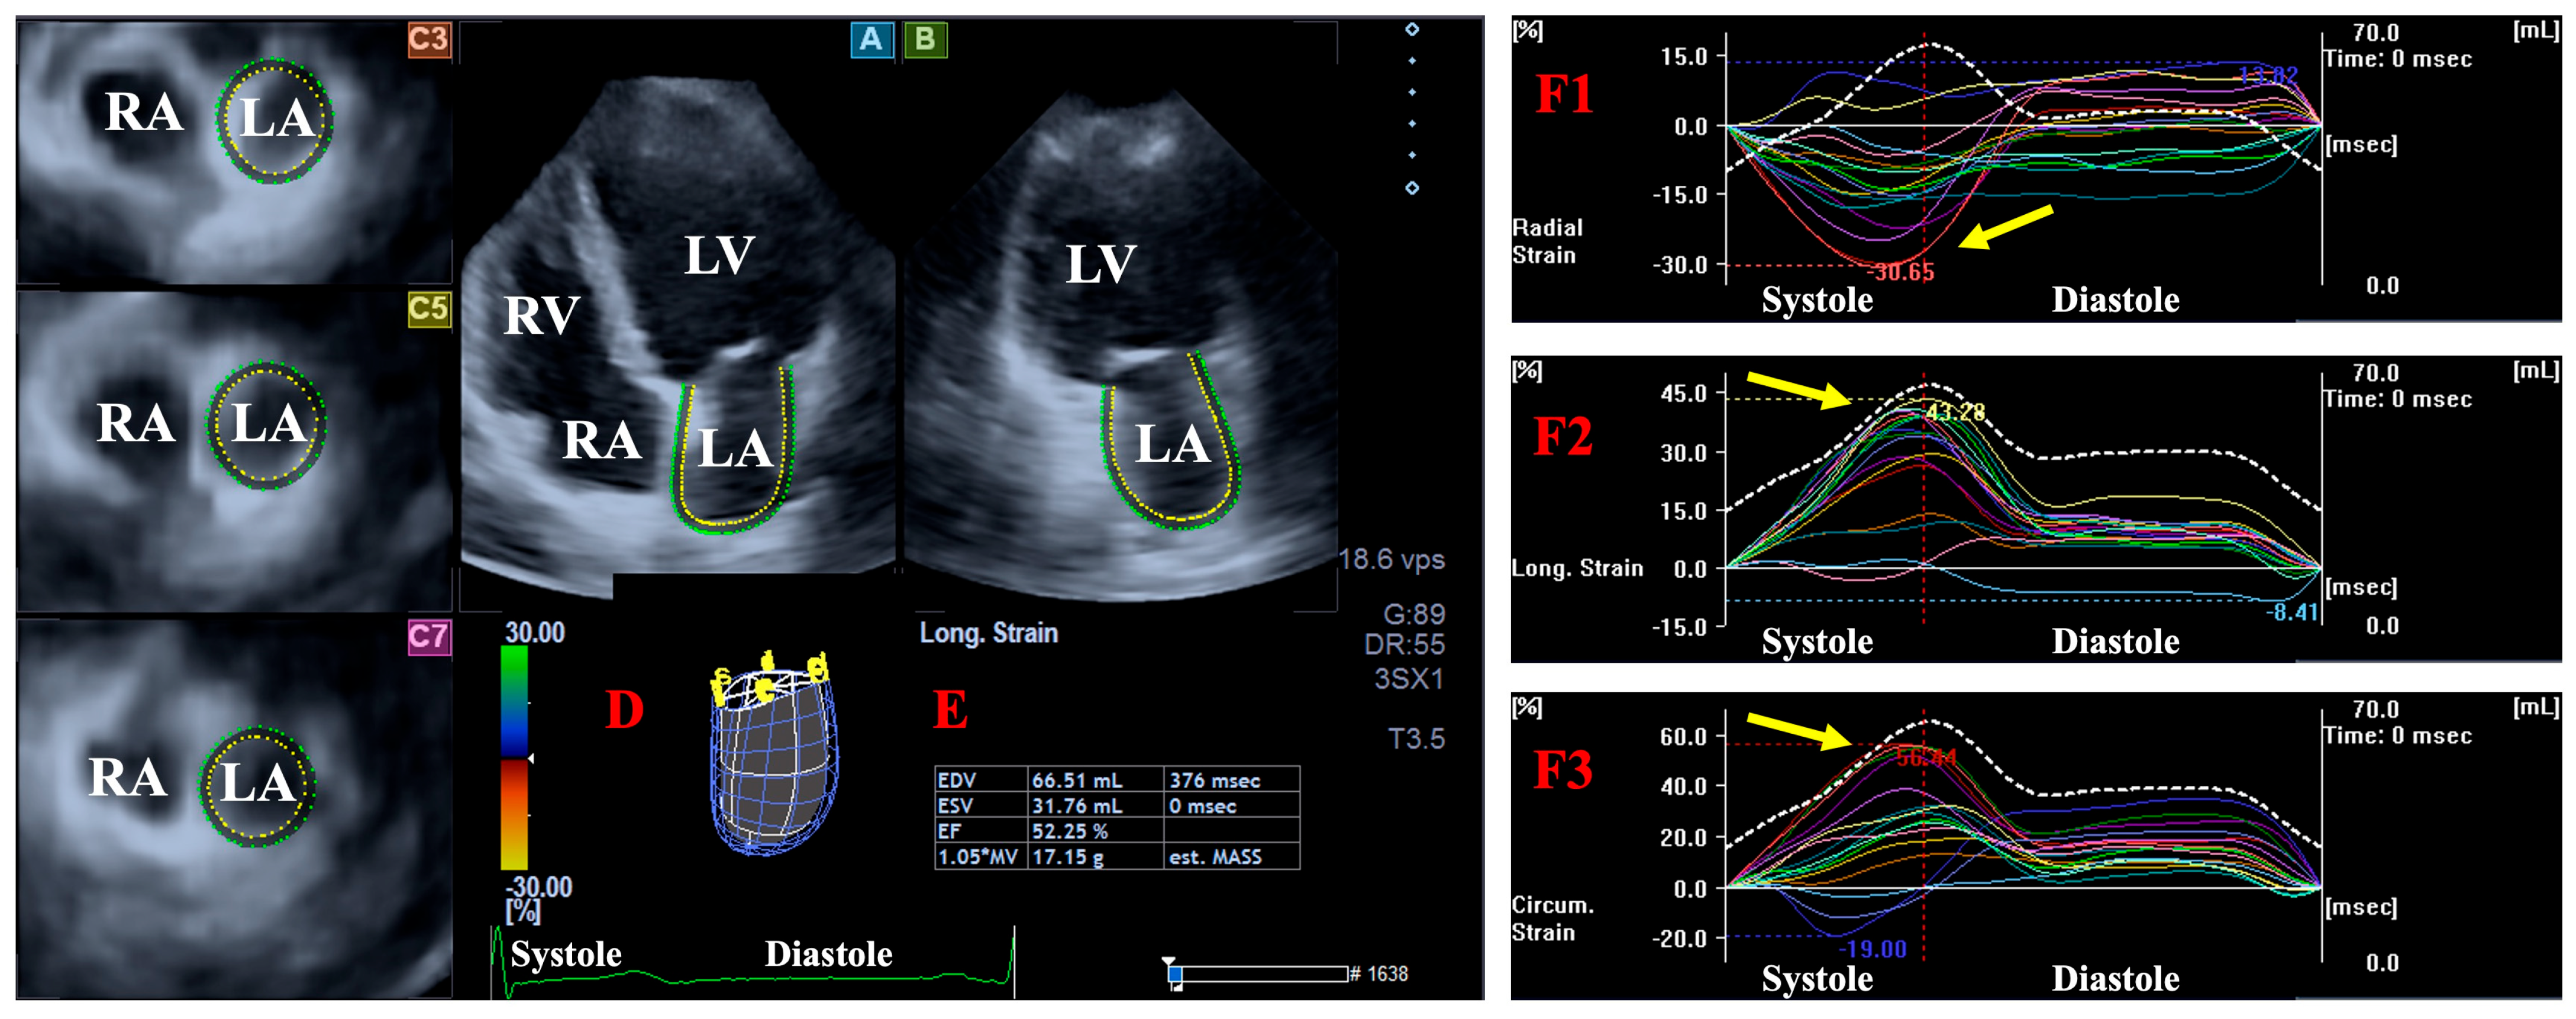

2.3. Three-Dimensional Speckle-Tracking Echocardiography

2.4. DSTE-Derived LA/LV Volumes and Strains

- LA/LV radial strain (LA/LV-RS), featuring the thinning/thickening of the myocardial tissue.

- LA/LV circumferential strain (LA/LV-CS), featuring the widening/narrowing of the myocardial tissue.

- LA/LV longitudinal strain (LA/LV-LS), featuring the lengthening/shortening of the myocardial tissue.